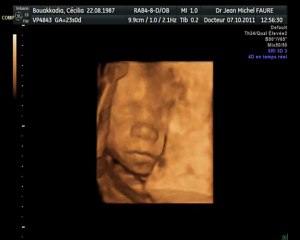

Echographie du second trimestre : fille ou garçon ?